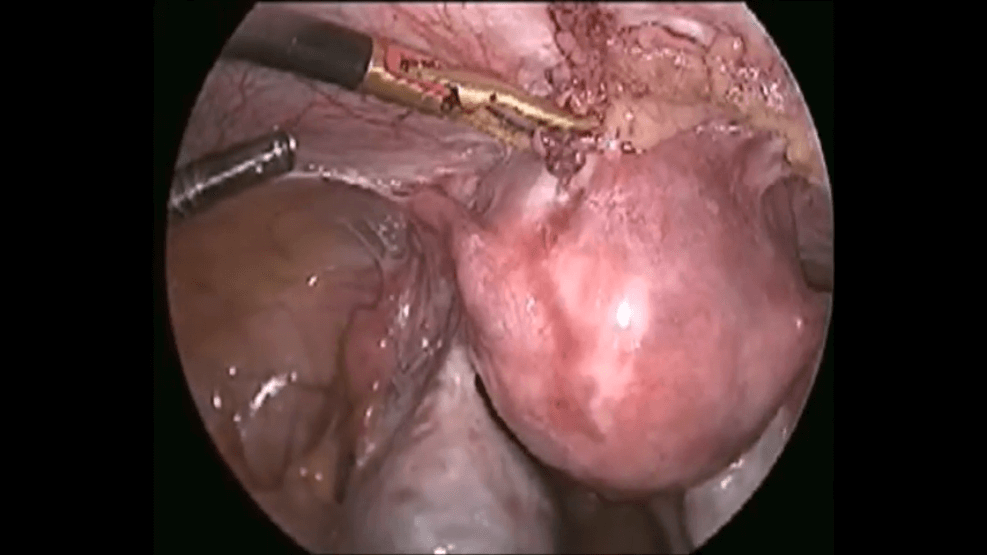

TLH IN ENDOMETRIOSIS - LIVE DEMONSTRATION